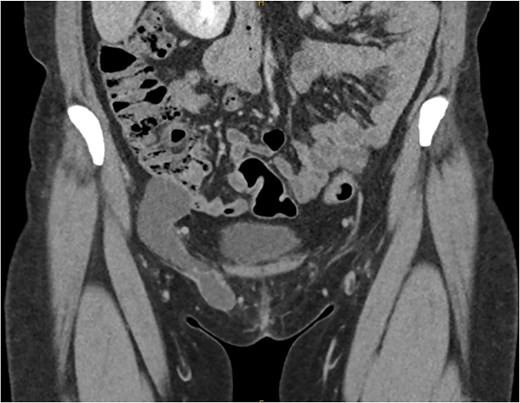

She had a computed tomography (CT) abdomen and pelvis with straining phase which demonstrated a bilobar cystic structed extending through the inguinal ring. The peritoneal component measured 46 × 35 × 33 mm and the inguinal measured 76 × 13 × 20 mm. There was no herniation of any intraperitoneal contents thus confirming the diagnosis of a hydrocele of the canal of Nuck (Fig. 1).

Coronal slice of CT demonstrating the bilobar right sided hydrocele of the canal of Nuck.